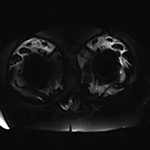

Inversion Recovery Imaging. (A) Axial spectral adiabatic inversion recovery (SPAIR) image used during MR examination of the abdomen and pelvis demonstrates large regions of susceptibility due to bilateral metal-on-metal hip arthroplasties as this technique is highly sensitive to field inhomogeneities.